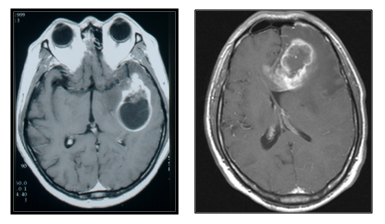

뇌교종(glioma)은 교세포라는 뇌구성 세포들에서 기원한 종양을 뜻하는 포괄적인 용어입니다. 뇌교종 중 절반 이상이 악성이며, 이러한 뇌교종 중, 빈도가 가장 많고 악성도 역시 가장 높은 악성 뇌교종이 교모세포종 (glioblastoma)입니다. 교모세포종은 성인에서 발생하는 원발성 두개강내 종양 중 약 1/4를 차지하는 비교적 흔한 종양으로 최신 치료법에도 불구하고 평균 생존 기간이 14개월 정도 되는 악성도가 매우 높은 종양입니다. 주로 40대 이상의 연령에 많으며 매년 인구 10만명당 5~6명의 발생 빈도를 보이는 것으로 알려져 있습니다.

※ 모세포종의 전형적인 MRI 소견 – 조영증강이 잘되며, 경계가 불규칙하고 내부에 조영증강이 잘되지 않는 괴사 부위를 포함하고 있고 주변으로 심한 뇌부종을 동반하고 하고 있음일반적으로 교모세포종의 수술적 치료의 목적은 1) 정확한 병리학적 진단 2) 두개강내압 상승과 뇌조직 압박에 의한 신경학적 증상의 완화 3) 방사선 및 항암화학요법의 치료 효과를 증대시킬 목적으로 시행하게 됩니다. 최근에는 형광유도물질을 이용하여 뇌종양세포만 선택적으로 제거하고 완전 절제율을 높이는 수술적 치료법도 많이 사용되고 있습니다.